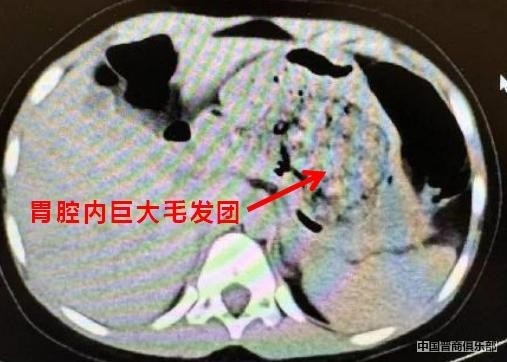

在得知孩子从小有吃自己头发的习惯之后,医生从CT片子上发现胃里有一团密度较高的团块,因此断定是孩子长期吃头发导致胃内毛发成团,引发腹痛。

手术发现,孩子胃内的毛发包裹着食物残渣,形成了一个巨大的团块,充满整个胃腔,花了3个多小时才清理干净,之后孩子顺利恢复正常。